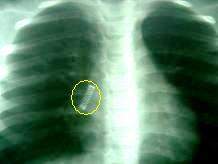

En los cuerpos extraños de la laringe, al realizar la laringoscopia aparece el cuerpoextraño; pero si son muy pequeños, pueden pasar inadvertidos. En este caso, si son opacos los descubre la radiografia.

El examen clínico en los cuerpos extraños bronquiales permite observar una limitación de la expansión torácica en el lado enfermo, o una hiperresonancia por enfisema obstructivo y desplazamiento del mediastino hacia el lado opuesto. En la auscultación se percibe ausencia o gran disminución de los ruidos respiratorios.

La radiogafia, sino es definitiva, ofrecerá datos sobre la situación del cuerpo extraño, y si este no es opaco, sobre la producción de una zona de atelectasia o enfisema.